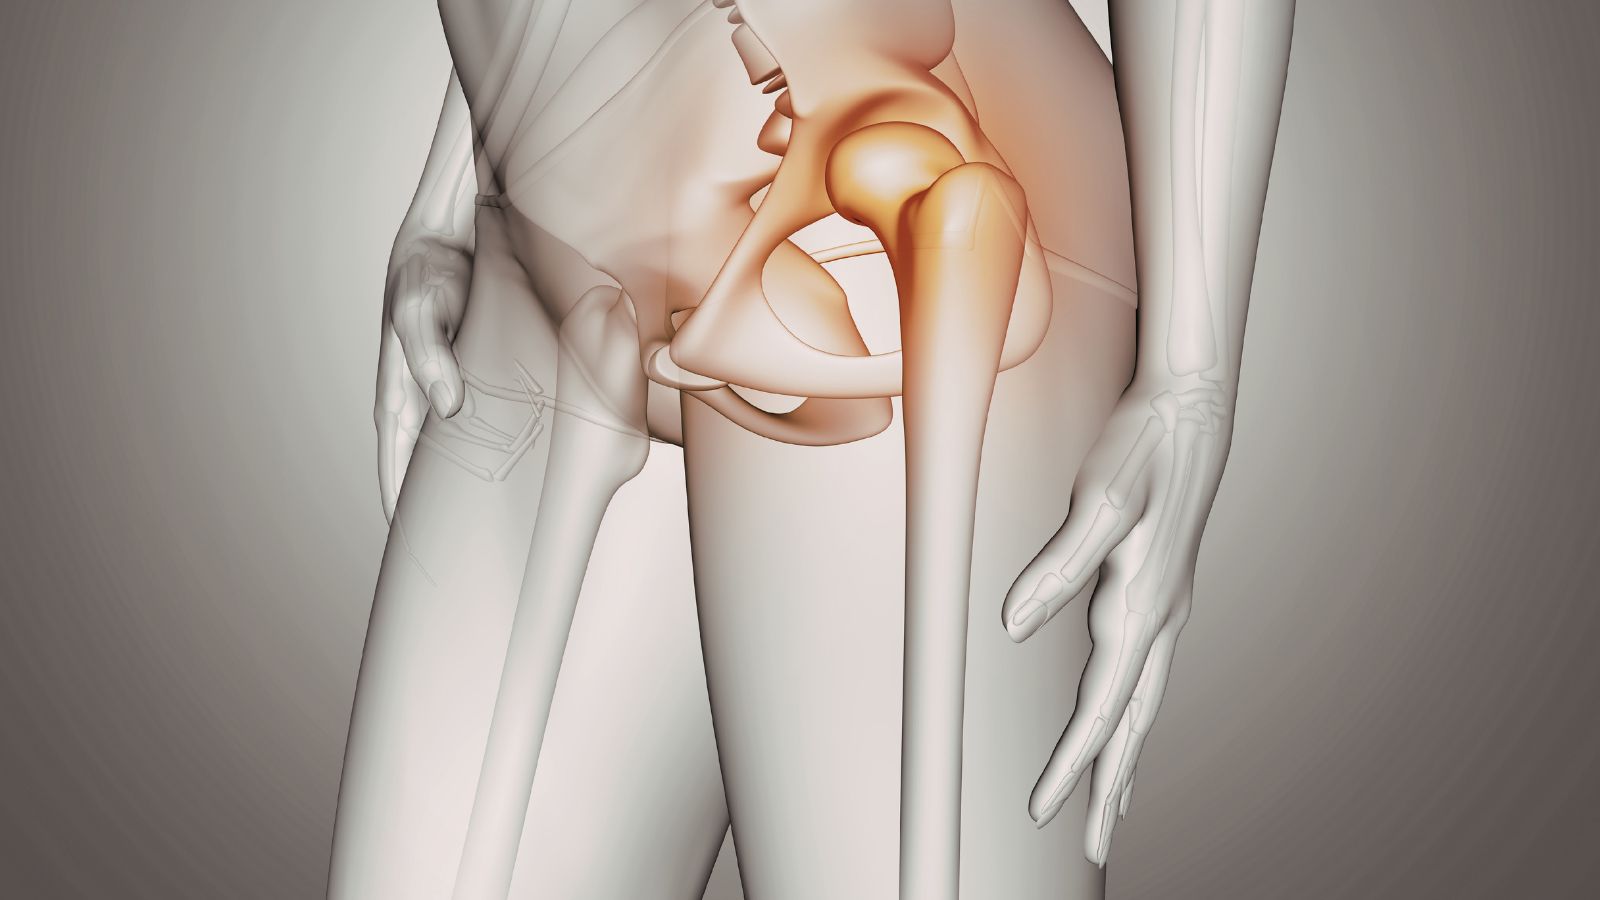

Hoại tử khớp háng (hoại tử vô mạch chỏm xương đùi) là tình trạng phần chỏm xương đùi bị thiếu máu nuôi dưỡng trong thời gian dài, dẫn đến tế bào xương chết dần. Khi máu không cung cấp đủ oxy và dưỡng chất, cấu trúc xương suy yếu, từ đó gây sụp lún chỏm xương và phá hủy khớp háng.

Khớp háng là khớp chịu lực lớn của cơ thể, giúp chúng ta đi lại, đứng, ngồi và xoay người linh hoạt. Khi hoại tử khớp háng xảy ra, chức năng vận động sẽ bị ảnh hưởng nghiêm trọng.